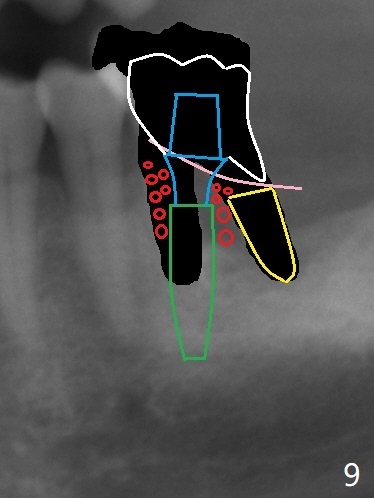

After tooth extraction (Fig.4), a medium-sized implant (4.5 mm, Fig.5 green) will be placed in the mesial socket, but the coronal end of the long axis of the implant (white line) will be in the middle of the socket for future restoration. The gingival margin of the socket is also uneven (Fig.6 pink). Before placement of the final abutment (Fig.7 blue), pack allograft (red circles) over the exposed implant surface until the platform of the implant. After placement of Osteogen plug in the distal socket (Fig.8 yellow), more of allograft is placed coronally. An immediate provisional (Fig.9 white) is to be fabricated to keep the graft in place. If the socket is deemed to be unsuitable for immediate implant, place PRF membrane(s) distoocclusally (Fig.10 purple), followed by collagen membrane and suturing.